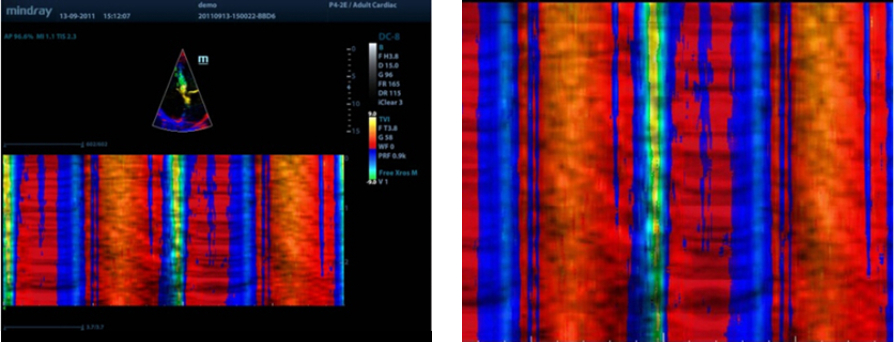

Free Xros CM?

Evaluación precisa del movimiento en diferentes fases y sincronización simultánea del miocardio. Provee alta velocidad de cuadros, proporcionando resultados precisos.